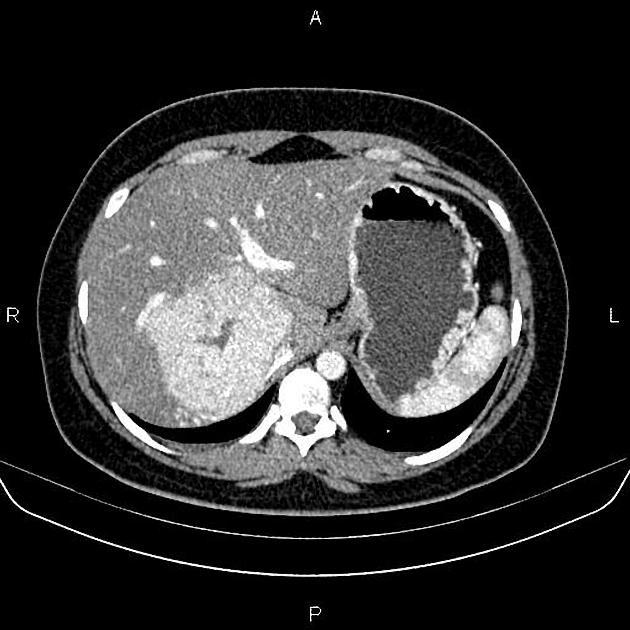

當(dāng)體檢報告上出現(xiàn)“肝臟占位性病變,FNH可能”這幾個字時,很多朋友的第一反應(yīng)是恐慌和焦慮,立刻聯(lián)想到最壞的可能性。FNH的中文名是“局灶性結(jié)節(jié)性增生”,其實是一種比較常見且完全良性的“肝臟小結(jié)節(jié)”。它更像是一個美麗的誤會,是肝臟自己長出來的一個“小疙瘩”,但絕非腫瘤。一、FNH是什么?——肝臟的一次“自我修復(fù)”我們的肝臟由無數(shù)肝細(xì)胞和膽管、血管組成。FNH的中央瘢痕本質(zhì)上是纖維結(jié)締組織增生,由異常血管結(jié)構(gòu)(如厚壁動脈、毛細(xì)血管畸形)引發(fā)的局部缺血和修復(fù)反應(yīng)。是肝臟局部血管結(jié)構(gòu)的細(xì)小異常(比如血管畸形或擴張),導(dǎo)致局部區(qū)域缺血。肝臟發(fā)現(xiàn)這里的血液循環(huán)不對勁,于是啟動了“自我修復(fù)”程序,過度地增生了一些正常的肝細(xì)胞、膽管和纖維組織,試圖把這個問題修補好。結(jié)果,修補得有點“過頭”,就形成了一個團結(jié)緊密的“小疙瘩”或“小星球”。最關(guān)鍵的一點:FNH不是癌癥,不會癌變,也不會擴散到身體其他部位。它是一個完全良性的“修復(fù)性”病變,是肝臟自己跟自己開的一個小小玩笑。二、有什么癥狀?——絕大多數(shù)沒有FNH最典型的特征就是“沉默是金”。絕大多數(shù)(約70%-80%)的FNH患者沒有任何癥狀。它們通常是在體檢做腹部B超、CT或MRI時被意外發(fā)現(xiàn)的。少數(shù)情況下,如果這個“小星球”長得特別大(比如超過5厘米),可能會壓迫到周圍的器官,引起輕微的右上腹隱痛、飽脹感或摸到包塊,但這種情況非常罕見。它不會影響肝功能,也不會導(dǎo)致乏力、消瘦、黃疸等嚴(yán)重問題。所以,沒有癥狀本身就是FNH的一個積極信號。三、如何確診?——火眼金睛的影像學(xué)診斷FNH最關(guān)鍵、最核心的環(huán)節(jié)是影像學(xué)檢查1.腹部B超作用:通常是發(fā)現(xiàn)FNH的“第一道哨兵”。B超能看到肝臟里有一個“占位”,但難以確定它的具體性質(zhì)。特點:FNH在B超下通常表現(xiàn)為邊界清晰的稍低或等回聲團塊,有時能看到中央的“星形瘢痕”。2.增強CT或MRI(磁共振)——診斷的“金鑰匙”這是確診FNH的王牌手段。FNH有一個非常特征性的表現(xiàn):“快進慢出”:在動脈期(注射造影劑早期),由于瘢痕無明顯強化,僅病灶實質(zhì)部分快速強化(因正常肝細(xì)胞血供豐富),它會迅速且顯著地均勻強化,變得非常亮,像一顆被點燃的小星星。“中央星狀瘢痕”:在門靜脈期和延遲期(注射造影劑中后期),整個“小星球”的亮度會降下來,變得和周圍肝組織差不多,但此時病灶中心動脈血流灌注異常,促使纖維組織呈放射狀分布,纖維瘢痕因?qū)Ρ葎┲饾u擴散至纖維間隙而呈漸進性強化,形成星芒狀瘢痕中央的纖維瘢痕會逐漸顯影,呈現(xiàn)典型的“星狀”或“放射狀”改變。這是FNH非常具有特征性的標(biāo)志。MRI對于顯示這個“中央瘢痕”尤其敏感,診斷準(zhǔn)確性非常高。如果增強CT或MRI影像報告提示符合FNH的典型特征,那么診斷的準(zhǔn)確性就極高(>95%),通常不需要再做穿刺活檢來確認(rèn)。四、預(yù)后與隨訪:和平共處一輩子這是最重要的一部分,請您放心:1.預(yù)后極佳:FNH的預(yù)后非常好。它不會惡變,不會影響您的壽命,也不會影響您的肝功能。您完全可以把它當(dāng)作身體的一個無害的“小標(biāo)記”,就像皮膚上的一顆痣一樣。2.需要治療嗎?絕大多數(shù)不需要任何治療!首選方案就是“和平共處,定期觀察”。只有在極少數(shù)情況下才考慮手術(shù)切除,例如:①腫塊巨大,并引發(fā)了持續(xù)、明顯的癥狀;②診斷不明確,無法完全排除其他疾?。虎刍颊咭蛩a(chǎn)生極度焦慮,嚴(yán)重影響生活。但這非常罕見。3.需要如何隨訪?如果影像學(xué)特征非常典型,且患者沒有癥狀,很多專家認(rèn)為甚至不需要頻繁隨訪。一個常見的保守隨訪建議是:在發(fā)現(xiàn)后的第6個月和第12個月分別做一次影像學(xué)檢查(如B超或MRI),如果大小、形態(tài)穩(wěn)定,之后可以每1-2年甚至更長間隔復(fù)查一次即可。如果一直穩(wěn)定,最終可以停止隨訪。您的任務(wù)就是正常生活,忘記它的存在。總結(jié)與溫馨提示如果您或您的家人被診斷出FNH,請記住以下幾點:1.它不是癌:請把心頭的大石放下,F(xiàn)NH是一個良性病變,是虛驚一場。2.它很常見:在偶然發(fā)現(xiàn)的肝臟占位中,F(xiàn)NH是僅次于肝囊腫和肝血管瘤的常見良性病變,很多人都有。3.診斷靠影像:增強CT/MRI是確診的利器,特征很明顯,醫(yī)生很有經(jīng)驗。4.相處靠觀察:無需吃藥、無需手術(shù),只需偶爾復(fù)查,和它和平共處。5.生活照常過:保持健康的生活方式(均衡飲食、適度運動、限制飲酒)對整體肝臟健康有益,但無需為FNH改變什么。